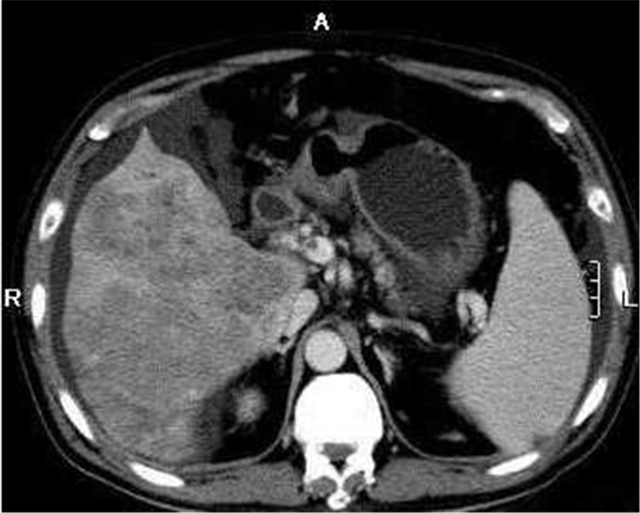

孙先生,34岁,主述近日来一直肝脏和肩胛骨部位钝痛,偶感恶心,食欲不振。我们经过肝脏核磁共振和甲胎蛋白等检查,基本 确诊为乙型肝细胞癌。

肝细胞肝癌(以下简称肝癌)是我国癌症的癌中之王。 肝癌(Liver cancer)是一种发生于肝脏的癌症。诱发肝癌的主要因素是病毒,我国全民要打的乙肝疫苗就是用来抗肝癌和预防肝癌。肝癌的主要发病就是由病毒引起炎症,进而引起肝炎,然后经过治疗,炎症再变成脓疱,脓疱然后结疤就形成了肝硬化,然后进一步形成了肝癌。

肝癌大致分为两类,原发性和继发性。肝脏中的细胞生长变异而形成癌症,这类源发于肝脏自身细胞的癌症被叫作原发性肝癌,包括下面几种:(1)肝细胞癌 :这是最常见的肝癌类型,部分肝细胞癌是从肝硬化发展而成的;(2)肝内胆管癌或胆管癌:占肝癌中的10%~20%;(3)血管肉瘤和血管内皮瘤:这种癌类很少发生,但是非常危险,它的分裂速度非常快,分布广泛,无法手术;(4)肝母细胞瘤:这种癌症非常罕见,主要发生在4岁以下的儿童身上。经过规范治疗,近2/3的患者能治愈。因为肝脏器腔内血流量很大,其他部位的癌症很大可能会移动到肝脏,就会形成继发性肝癌(转移性肝癌)。这类继发性肝癌症与原发性肝癌特征基本相同。